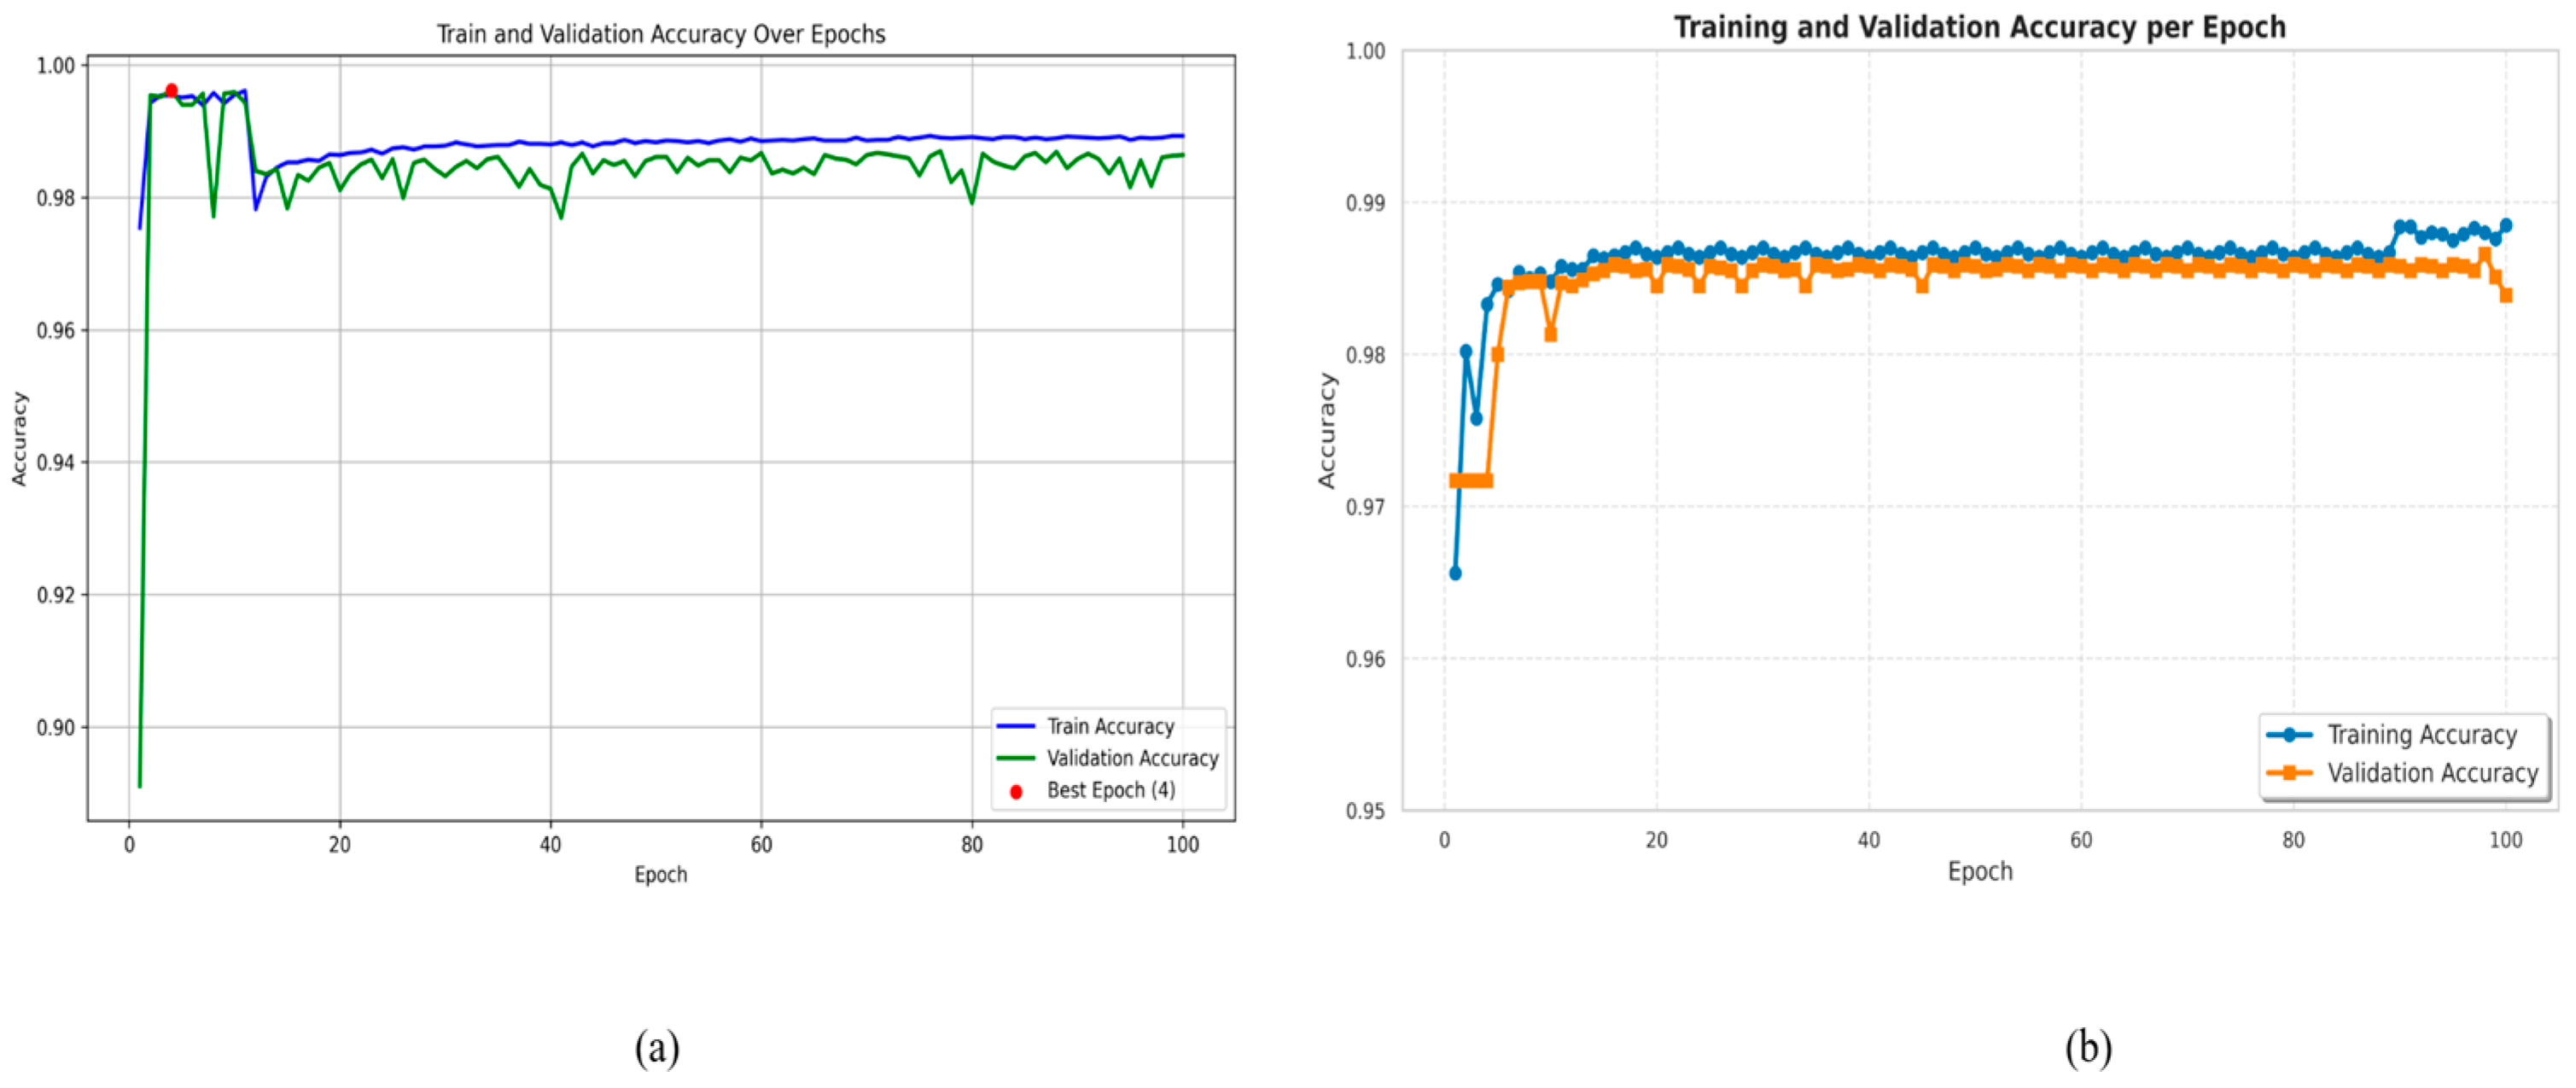

4. Experimental Results and Discussions

4.1. Implementation

4.2. Ablation Study

4.5. Analysis Using Different Optimizers

4.6. Cross-Dataset Generalization Study